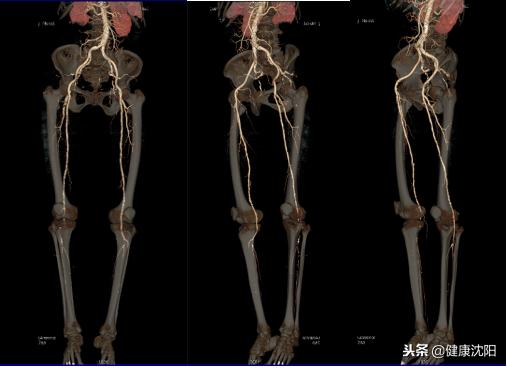

VR三维显示可以直观显示血管的大体形态、解剖,可以对病变进行明确的定位、定性诊断,可以直观地显示血管狭窄、血管瘤、动静脉畸形等病变,还可以间接判断血管壁的病变,进而提供进一步检查的必要性。CTA检查的VR技术实现了无创检查就能了解自己血管形态的目的。

显示腹主动脉及双侧下肢血管影像与骨骼影像VR主次重叠显示